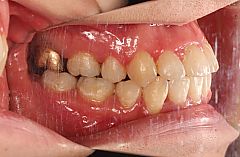

下顎中切歯が上顎中切歯よりも前に位置しているため下顎前突といえますが、骨格性の下顎前突傾向を有しているわけではなく、あくまで歯の傾きによる下顎前突(歯性の下顎前突症)です。横から見たときに上顎前歯が若干舌側に傾斜しています。

上顎両側犬歯の低位唇側転位(八重歯)、上顎両側側切歯の舌側転位、下顎左側犬歯の低位唇側転位、下顎両側側切歯の舌側転位が認められます。また、歯磨きがしにくいのでしょうか、治療前の口腔内写真をみると上顎中切歯付近の歯肉に炎症が認められます(歯肉炎)。

治療期間は24か月間でした。治療後の写真を見ると上顎前歯部の発赤が緩和され、ピンク色に変化しています(健康な歯肉はピンク色です)歯肉炎が改善されていることが分かります。この写真は矯正装置撤去直後の写真ですから今後はもっと良くなることが期待できます。